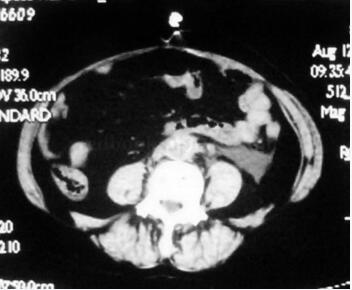

腹部CT平扫(图45-2):腰椎体前方腹主动脉、下腔静脉、髂总血管周围的腹膜后及盆腔间隙可见软组织影,同时包绕左侧输尿管。

图45-2 腰椎体前方腹主动脉、下腔静脉、髂总血管周围的腹膜后及盆腔间隙可见软组织影,同时包绕左侧输尿管

(2)IRF不同病理阶段的CT表现不同,在纤维早期时,表现为腹膜后间隙境界不清的弥漫性低密度影(与肌肉密度类似);中晚期时,表现为腹膜后或盆后间隙境界清楚的低、不均或等密度不规则软组织肿块影,呈对称或非对称性分布。增强后,早期病灶增强多较明显,晚期(成熟期)几乎无强化。因此CT是目前诊断该病及其病变进展的有效方法。